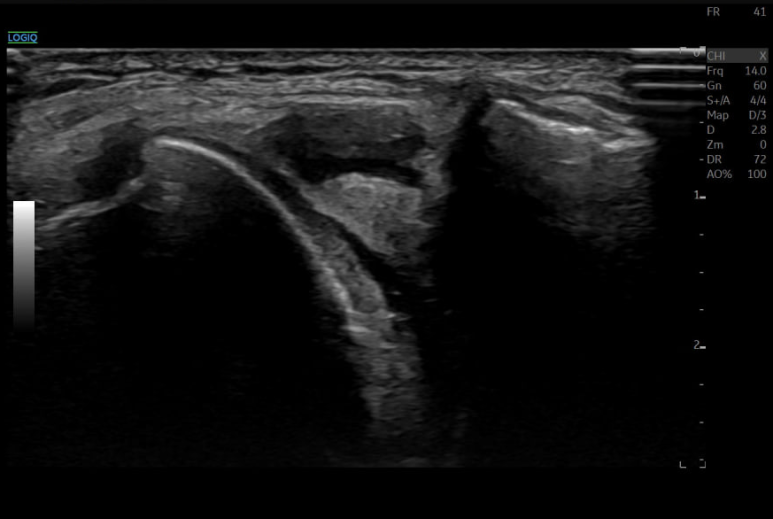

Totus 이미지

얕은 부분과 깊은 부분 모든 범위를

빠르게 처리하기 때문에

Focus 버튼 자체가 없습니다.

포커싱이 없이도

영상 전체를 최적화해줍니다.

동일 셋팅으로

이미지 추출해서 비교해본 결과

해상도 차이가 없습니다.